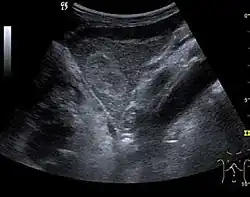

Liver cyst

The ultrasound appearance is a well defined lesion, with very thin, almost unapparent walls, without circulatory signal at Doppler or CEUS investigation. The content is transonic suggesting fluid composition. The presence of membranes, abundant sediment or cysts inside is suggestive for parasitic, hydatid nature. Posterior from the lesion the acoustic enhancement phenomenon is seen, which strengthens the suspicion of fluid mass. They typically displace normal liver vessels but no vascular or biliary invasion occurs.

They can be single or multiple, with variable size, generally less than 20 mm (congenital). Rarely, sizes can reach several centimeters, leading up to the substitution of a whole liver lobe (acquired, parasitic). They may be associated with renal cysts; in this case the disease has a hereditary, autosomal dominant transmission (von Hippel Lindau disease).